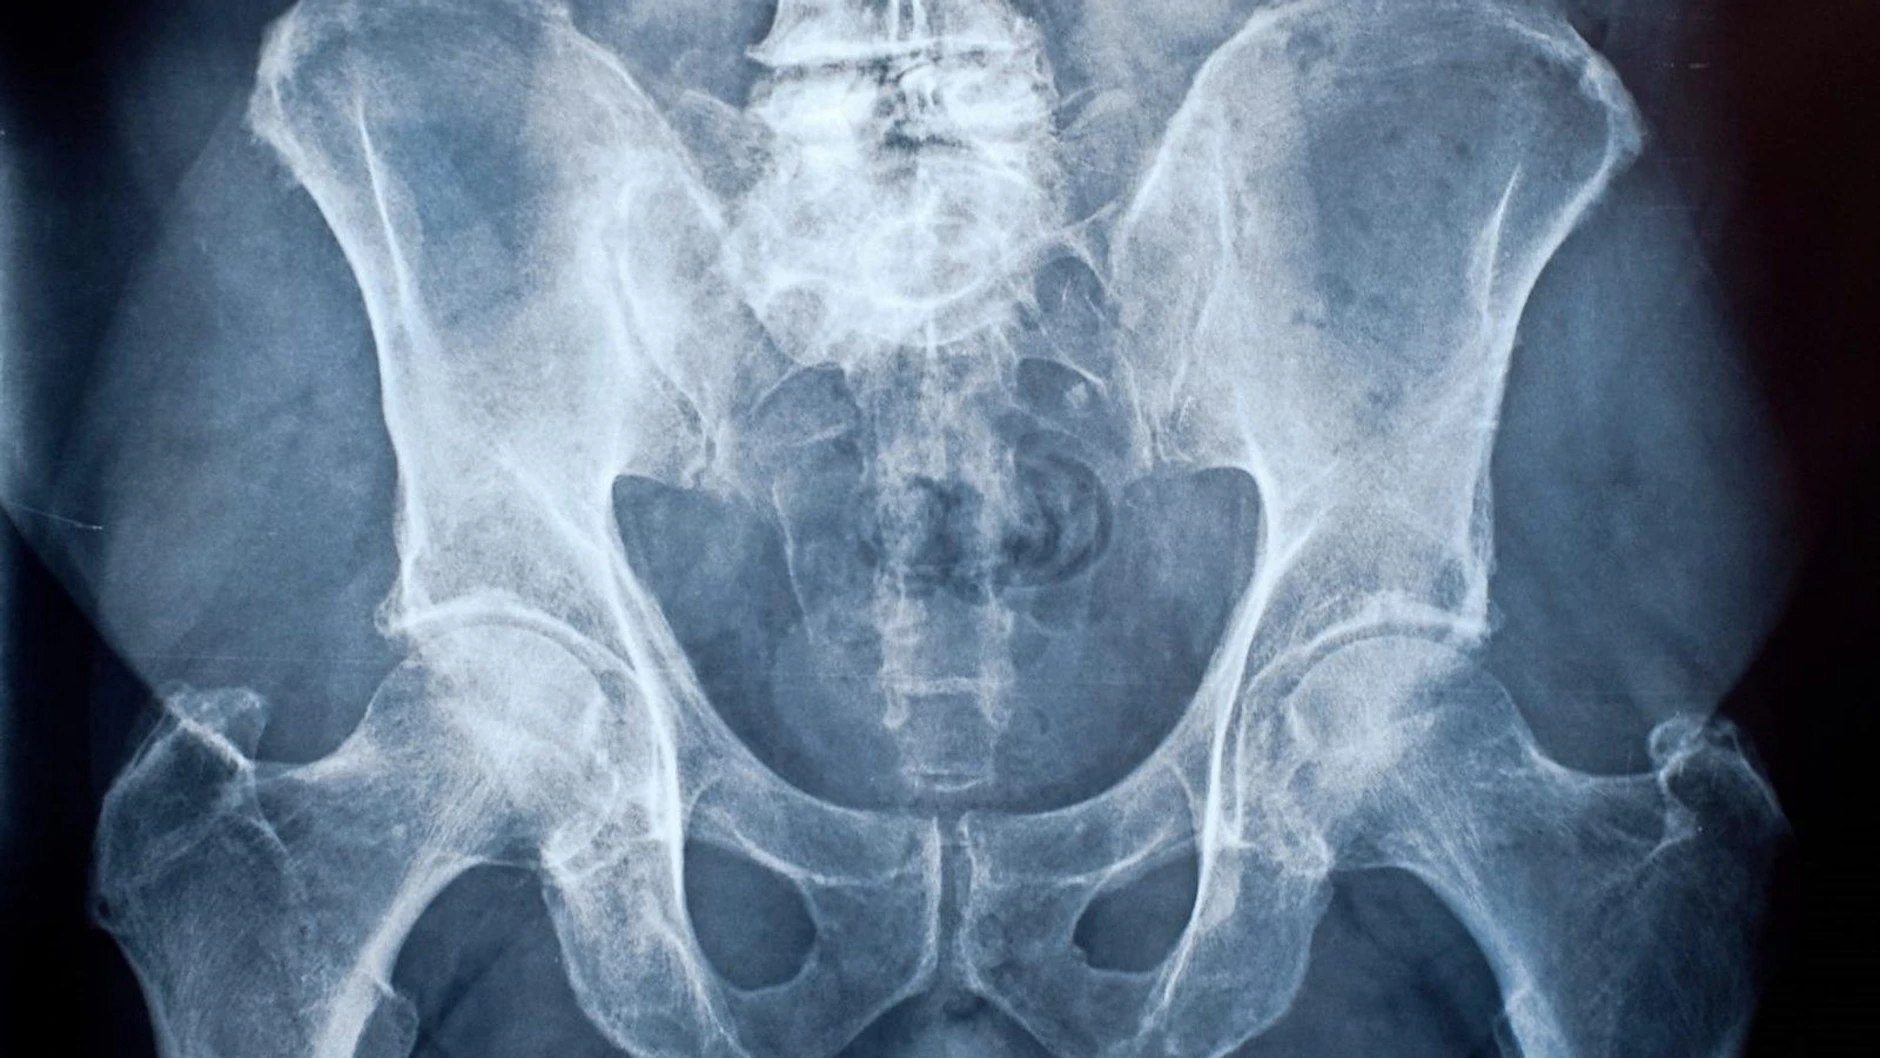

Knochensarkome treten recht häufig bei Kindern auf

Auch wenn Sarkome selten sind: Bei Kindern und Jugendlichen zählen Knochensarkome mit einem Anteil von zwölf bis 15 Prozent zu den häufigsten Krebserkrankungen. Bei älteren Patienten überwiegen dagegen die Weichgewebesarkome. Sie stellen in Deutschland bis zu 4000 der jährlich knapp 5000 Sarkom-Neudiagnosen.